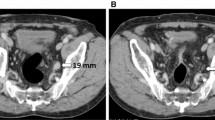

PET/MRI is superior to CS for upstaging from M0 to M1 in the liver and for clarifying indeterminate lesions detected by CS. The patient was a 61-year-old woman, and abdominal ceCT revealed one indeterminate liver lesion (a; red arrow). PET/MRI revealed that this lesion was positive with restricted diffusion and high FDG uptake (c, d; yellow arrows). PET/MRI also revealed two other liver lesions with similar characteristics (c, d; yellow arrows). These lesions were confirmed by imaging follow-up